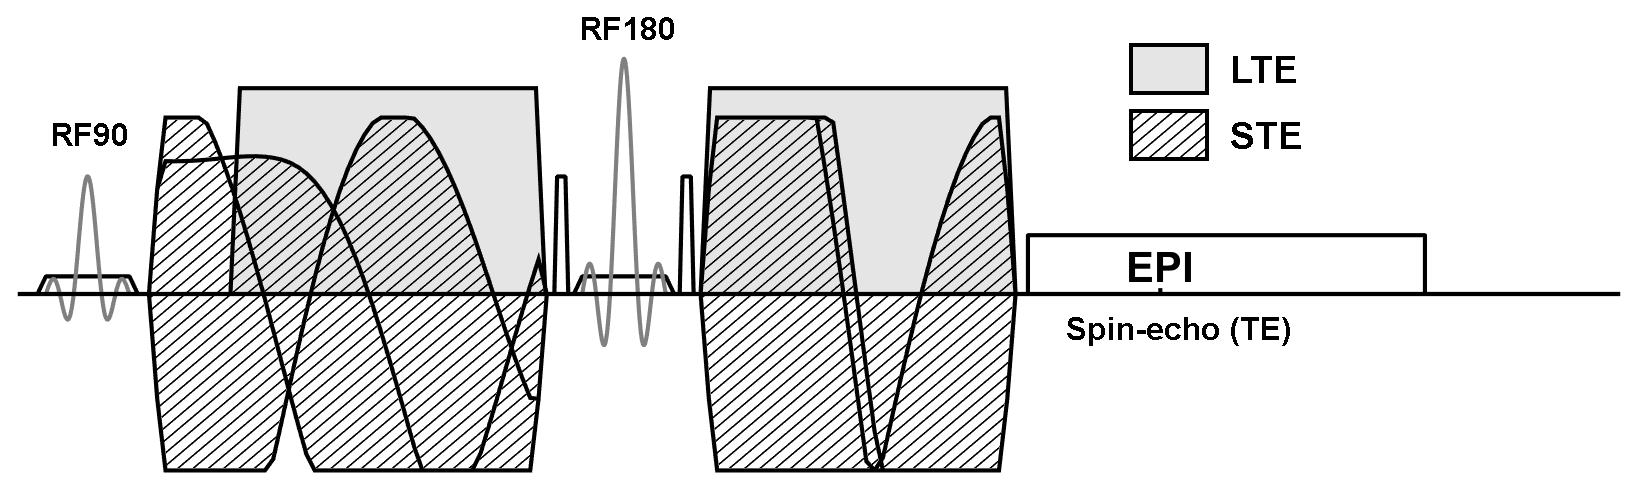

Tensor-valued diffusion encoding is an emerging technique within diffusion MRI. The novelty lies in the multidimensional encoding of the diffussion process. To support such encoding, we must replace the conventional diffusion encoding sequence with arbitrary gradient waveforms that facilitate a large range of encoding strategies. In doing so, we also need to store new kinds of experimental information to support traceability. In this project, we will extend the MRI pulse sequence to calculate and embed several necessary parameters in the DICOM header.